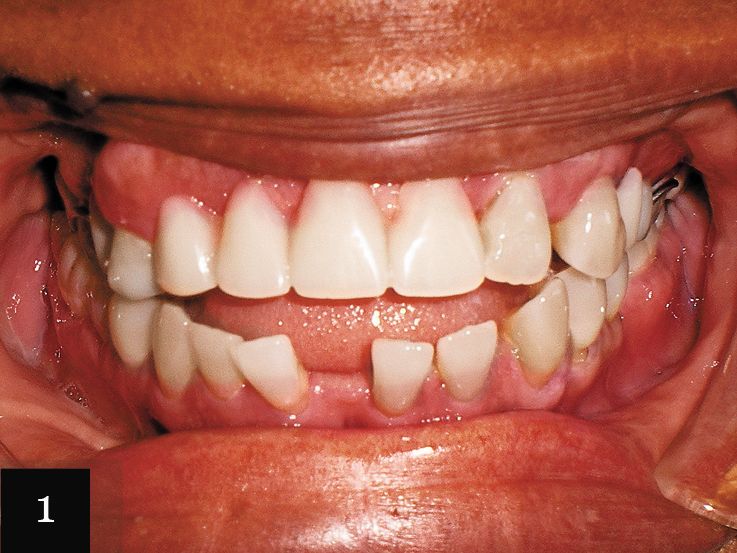

Case No. 1

This patient was a 55-year-old woman with a large space in her lower arch (Fig. 1). Despite this space, the patient was not missing any teeth. Figure 2 shows the impression-taking challenge-capturing the distal edge of the molars while also capturing the forward angle of the front teeth.

The impression was successfully captured on the first try, and the patient was treated with a series of 32 aligners over 16 months. The final result shows the closed space in the mandible and the dramatic esthetic improvement (Figs. 3 and 4).